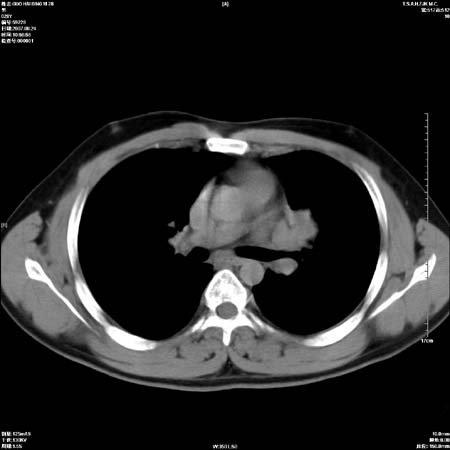

男性,28岁,体检发现左肺病变,患者只有背部隐痛感,哀哉,真不忍心下诊断啊。

左肺门区软组织肿块,左肺上叶支气管开口消失,纵隔内见肿大淋巴结,考虑左中心型肺部,可以做纤支镜取病理确认.

左肺肺门区肿块影,分叶明显,左肺上叶支气管开口受压,纵隔内见肿大淋巴结,考虑左中心型肺癌。

左侧肺门区见一块状病灶可见分叶,纵隔内及左肺门见肿大淋巴结,应该是周围型肺癌而不是中心型肺癌,原因有以下2点,1未见阻塞肺气肿和阻塞性炎症,这么大肿块如果是中心型肺癌就是未分化型或小细胞型肺癌不出现阻塞性肺不张也应该有阻塞炎症或阻塞性肺气肿,2如果是中心型肺癌临床出现最早的症状是咳嗽(此时可无任何异常影象),而此人这么大肿块只有背部隐痛是体检才发现无法解释.

左肺门区分叶状软组织肿块,纵隔内有肿大淋巴结,诊断肺癌应该问题不大。

直接下肺癌诊断还太早,病灶较大,估计5cm以上,但阻塞性改变及对临近纵隔及支气管侵犯不明显,密度较均匀,弓旁见一单个淋巴结,需要排除炎症性肿块及腺瘤,平滑肌瘤等。